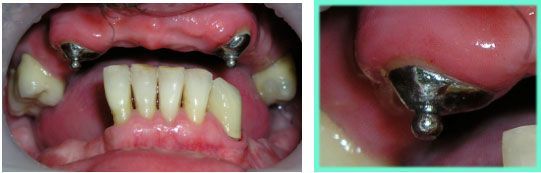

На этих снимках показана ответная часть вкладки – микрозамка.

Вкладка крепится на специальный цемент и является опорно-удерживающим элементом бюгельной конструкции.

Вид нижнего и верхнего бюгельных протезов